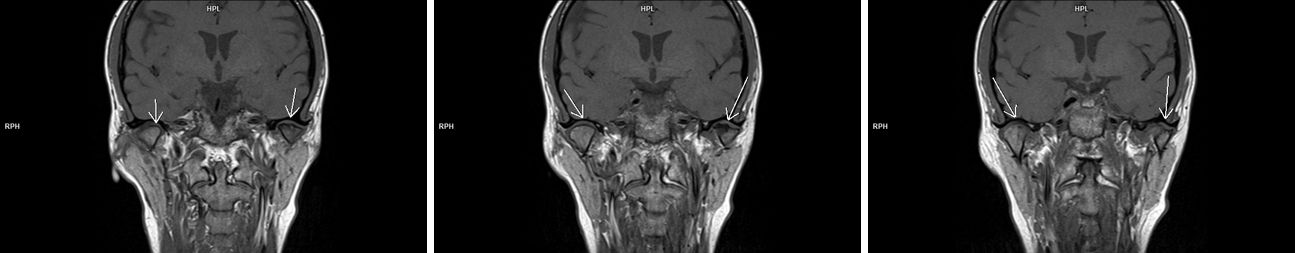

Figura 1: achiziţie oblic coronal T1 în planul articulațiilor temporo-mandibulare

Pe imaginile și secvențele cine prezentate se evidențiază modificare de formă a condilului mandibular stâng ce şi-a pierdut sfericitatea şi asociază prezenţa de modificări de tip edematos-inflamator în osul subcondral – modificare apărută probabil datorită unei asimetrii dentare astfel încât apare incongruența suprafețelor articulare iar pacientul prezintă cracmente articulare și blocare periodică a articulației; în principiu, asimetriile dentare (mușcături incorecte) duc în timp la probleme ale articulației, din cauza faptului că articulația este foarte mult solicitată.